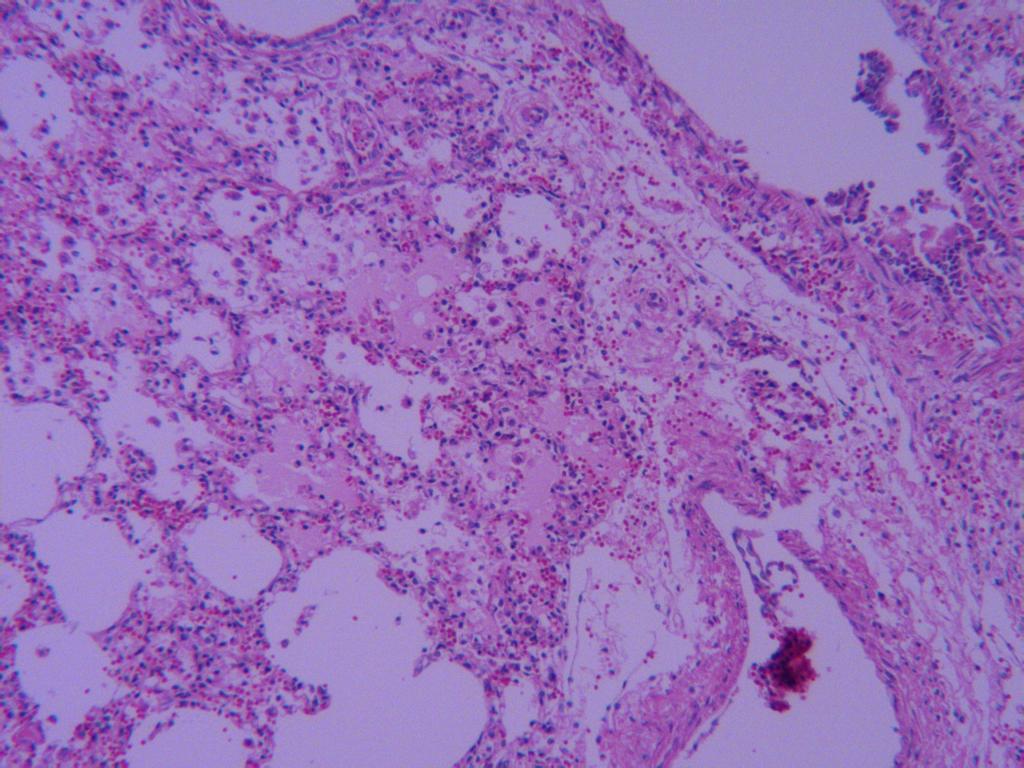

纤维素性肺炎

肺泡腔有大量淡红染的浆液和纤维素,并可见数量不等的红细胞和肺泡壁上皮细胞。

肺泡腔有大量红染的浆液,肺泡壁毛细血管扩张充血。

肺泡腔有浆液和纤维素,肺泡壁毛细血管扩张充血。

肺泡壁毛细血管扩张充血